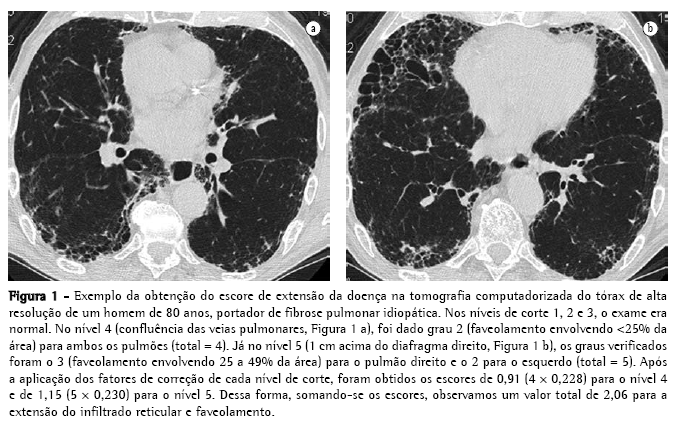

Ao final, somando-se os escores de cada nível, obteve-se os valores de Tot, Ret+Fav e Vif. Um exemplo da obtenção desses escores é mostrado na Figura 1.

FPI pela TCAR apenas mediante a concordância de todos os leitores e o preenchimento dos critérios clínicos e funcionais acima descritos. Inicialmente, a TCAR foi analisada de forma geral (sem considerar níveis de corte), procurando-se os seguintes achados: nódulos, opacidades em vidro fosco, infiltrado reticular, faveolamento (cistos <3 mm e >3 mm), bronquiectasias de tração, áreas de aprisionamento de ar e enfisema.(18,19) Posteriormente, a TCAR foi avaliada quanto à extensão e intensidade do envolvimento pulmonar intersticial, considerando-se cinco níveis de corte: 1) origem dos grandes vasos; 2) croça da aorta; 3) carina; 4) confluência das veias pulmonares; e 5) 1 cm acima do diafragma direito.(6,19-21) Através de um sistema de avaliação semiquantitativa, cada um desses níveis (direito e esquerdo, separadamente, totalizando 10 níveis) foi analisado quanto aos seguintes aspectos:

Escore de extensão total da doença intersticial (Tot) (incluindo infiltrado reticular, faveolamento, vidro fosco e outras alterações):

0) nenhuma alteração;

1) doença intersticial envolvendo =5% da área;

2) doença intersticial envolvendo 6 a 25% da área;

3) doença intersticial envolvendo 26 a 49% da área;

4) doença intersticial envolvendo 50 a 75% da área; e

5) doença intersticial envolvendo >75% da área.(10,22,23)

Escore de extensão do infiltrado reticular e faveolamento (Ret+Fav):

0) nenhum infiltrado reticular ou faveolamento;

1) infiltrado reticular sem nenhum faveolamento;

2) faveolamento (com ou sem infiltrado reticular) envolvendo <25% da área;

3) faveolamento envolvendo 25 a 49% da área;

4) faveolamento envolvendo 50 a 75% da área; e

5) faveolamento envolvendo >75% da área.(10,22,23)

Para a análise dos dados da TCAR, a estimativa do envolvimento pulmonar foi obtida mediante a aplicação de um fator de influência ('peso') para corrigir as diferenças dos volumes pulmonares em cada nível, conforme se segue(19):

origem dos grandes vasos - peso = 0,129;

croça da aorta - peso = 0,190;

carina - peso = 0,222;

confluência das veias pulmonares - peso = 0,228; e

1 cm acima do diafragma direito - peso = 0,230.